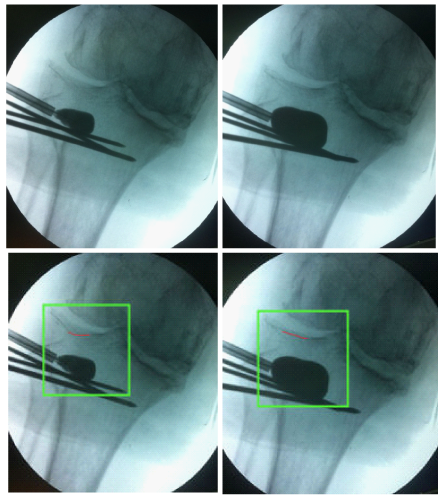

The optimal position for balloon placement was predetermined using the CT scanning. In the operating room the patient was placed in supine position on the operating table and a fluoroscopic unit was readily available. Under spinal anesthesia, a clinical stability test was applied, which did not reveal any ligamentous injury. After skin preparation and draping, a trocar was introduced in the lateral tibial plateau through a stub incision and advanced to the predetermined position - below the depressed fragment - using fluoroscopic control. Three Kirschner wires were placed just below the trocar, to act as a palisade, supporting the subsequent balloon inflation (Figure 2). We started slowly inflating the balloon with contrast solution to an initial pressure of 50 psi, without any radiographic evidence of balloon asymmetry, indicative of malpositioning. We then fully inflated the balloon to approximately 250psi, effectively raising the depressed tibial plateau (Figure 3).

Figure 3 Balloon inflation and fracture reduction (outlined by the red line).